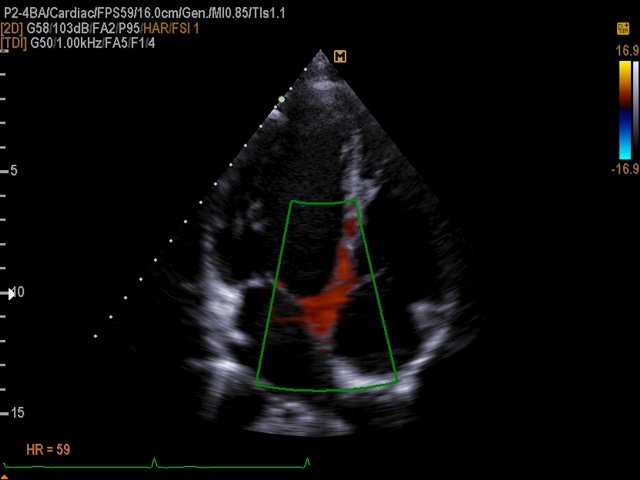

[RU] Ultrasound image №509: Interventricular septum movement (apical view) in TDI color doppler mode .

Echogramm was received by ultrasound scanner EKO7 (out of production).